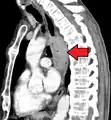

Esophageal cancer as shown by a filling defect during an upper GI series

Additional testing is needed to assess how much the cancer has spread (see § Staging, below). Computed tomography (CT) of the chest, abdomen and pelvis can evaluate whether the cancer has spread to adjacent tissues or distant organs (especially liver and lymph nodes). The sensitivity of a CT scan is limited by its ability to detect masses (e.g. enlarged lymph nodes or involved organs) generally larger than 1 cm.[41][42] Positron emission tomography is also used to estimate the extent of the disease and is regarded as more precise than CT alone.[43] Esophageal endoscopic ultrasound can provide staging information regarding the level of tumor invasion, and possible spread to regional lymph nodes.